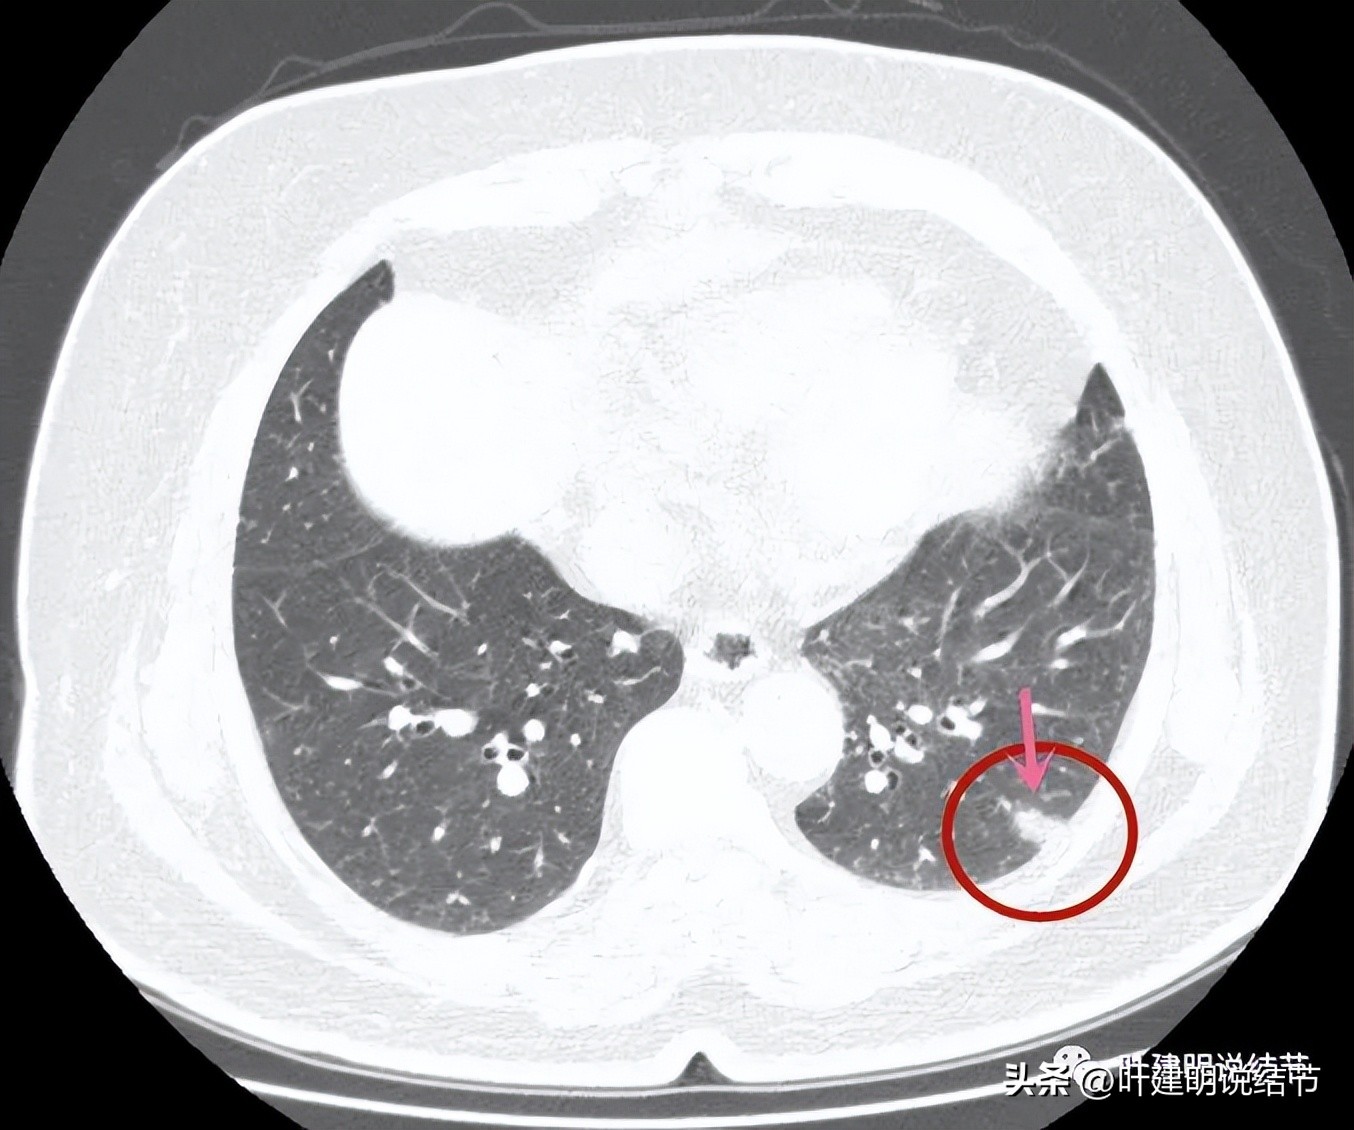

病灶表面不是很平整,整体密度较高,胸膜间隙征存在。

病灶有血管进入,但血管是逐渐变细的,不是异常增粗。而且病灶的几条边都比较平直,缺乏膨胀性。与胸壁也是紧贴,没有造成牵拉或侵犯影响。

边缘平直,血管进入变细

边缘平直似梯形

与胸壁接触的面较宽,余边也平直。

冠状位显示病灶不是很密实,表面是不平的,但毛刺略偏长,收缩力不够

整体缺乏膨胀感